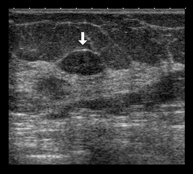

Breast ultrasound

This imaging method uses sound waves create an image of blood vessels, tissues and organs, including the breasts. Ultrasound imaging allows for the evaluation of abnormalities detected by mammography or clinical examination, distinguishing between solid and fluid lesions (cysts).

Ultrasound-guided FNA (fine-needle aspiration)

In fine needle aspiration (FNA), a thin needle is inserted under ultrasound guidance into a suspicious area of the breast; a syringe is then used to extract a small amount of tissue, which is sent for cytological examination. It is also used to puncture and drain breast cysts and analyse their contents. The procedure lasts only a few minutes and causes slight discomfort.